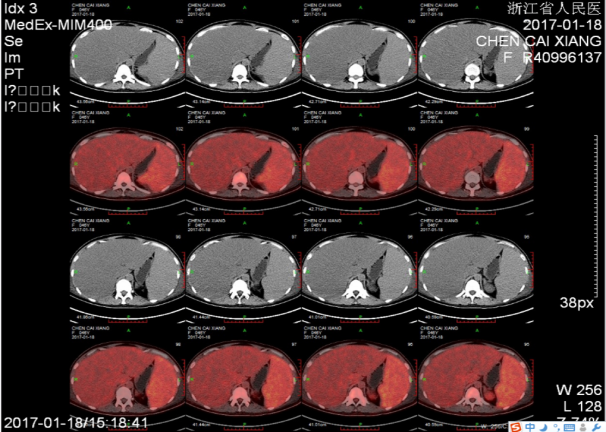

2017-01-18行PET-CT检查提示:

➤脾肿大伴FDG代谢活跃,SUV最大值约4.5,血液系统疾病可能,必要时活检;全身骨弥漫性FDG代谢活跃,SUV最大值约4.8,请结合骨穿。

➤左颈部、腹膜后和腹腔内散在淋巴结,FDG代谢活跃,反应性表现可能,请结合脾脏病理考虑。

➤脂肪肝,肝肿大,请结合临床。

➤双侧胸腔积液

,双下肺少许不张。慢性胆囊炎。腹盆腔积液。盆腔左侧囊性灶,FDG代谢未见异常,考虑良性,卵巢囊肿首先考虑。全身多发皮下水肿。双肾和双侧输尿管显像剂排泄缓慢(图3)。

图3